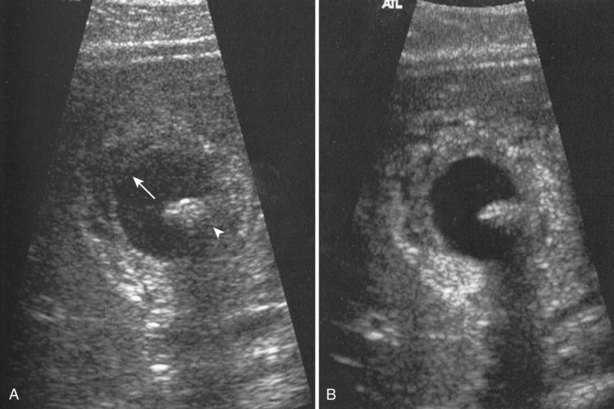

Harmonic scanning makes use of aberrations related to the nonlinear propagation of sound waves within tissue. These asymmetrically propagated waves generate fewer harmonics, but those that are generated have greater amplitudes. Because these harmonics are not subject to scattering associated with the incident wave, there is less noise associated with the signal. By concentrating on the harmonic frequencies produced within the body and reflected to the transducer, it is possible to produce an image with less artifact and greater resolution (Fig. 4–27).

Figure 4–27 A, Standard gray-scale image of a cyst containing a mural nodule (arrowhead). Note the artifactual echogenicity within the cyst (arrow). B, The same structure on harmonic scanning is more clearly seen. There is less artifact within and distal to the cyst.